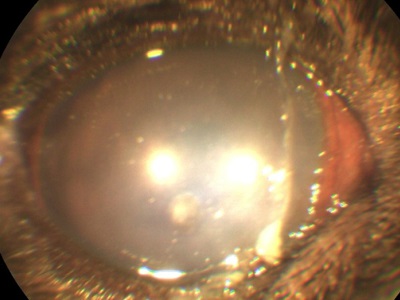

Cheratita (inflamarea corneei) la câini și pisici, de asemenea, dat o culoare albă din cauza umflarea, impregnează celulele corneene ale sistemului imunitar, vasele de sânge germinare. Keratită pot apărea datorită infecții, tulburări ale sistemului imunitar, pleoape sau gene traumatizării constante ale corneei și așa mai departe.

Este foarte important să se lucreze la boala este cauza cea mai mare pentru eficacitatea luptei.

acumulare de săruri în suprafață și straturile profunde ale corneei, de asemenea, o vopsea albă.

Aceste modificări apar ca urmare a inflamatiei cronice, genetica, tulburări ale metabolismului, tulburări endocrine. Pentru fiecare cauză are propriile sale de cercetare și algoritmul acțiunilor.